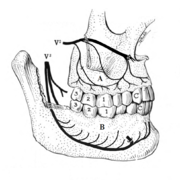

1: crown, 2: root, 3: enamel, 4: dentin and dentin tubules, 5: pulp chamber, 6: blood vessels and nerve within root canal, 7: periodontal ligament, 8: apex and periapical region, 9: alveolar bone.

V2: maxillary division of trigeminal nerve, V3: mandibular division of trigeminal nerve, A: the superior alveolar nerves and plexus, B: the inferior alveolar nerve and plexus running in the body of the mandible.

A tooth is composed of an outer shell of calcified hard tissues (from hardest to softest: enamel, dentin, and cementum), and an inner soft tissue core (the pulp system), which contains nerves and blood vessels. The visible parts of the teeth in the mouth — the crowns (covered by enamel) — are anchored into the bone by the roots (covered by cementum). Underneath the cementum and enamel layers, dentin forms the bulk of the tooth and surrounds the pulp system. The part of the pulp inside the crown is the pulp chamber, and the central soft tissue nutrient canals within each root are root canals, exiting through one or more holes at the root end (apical foramen/foramina). The periodontal ligament connects the roots to the bony socket. The gingiva covers the alveolar processes, the tooth-bearing arches of the jaws.[41]:1–5